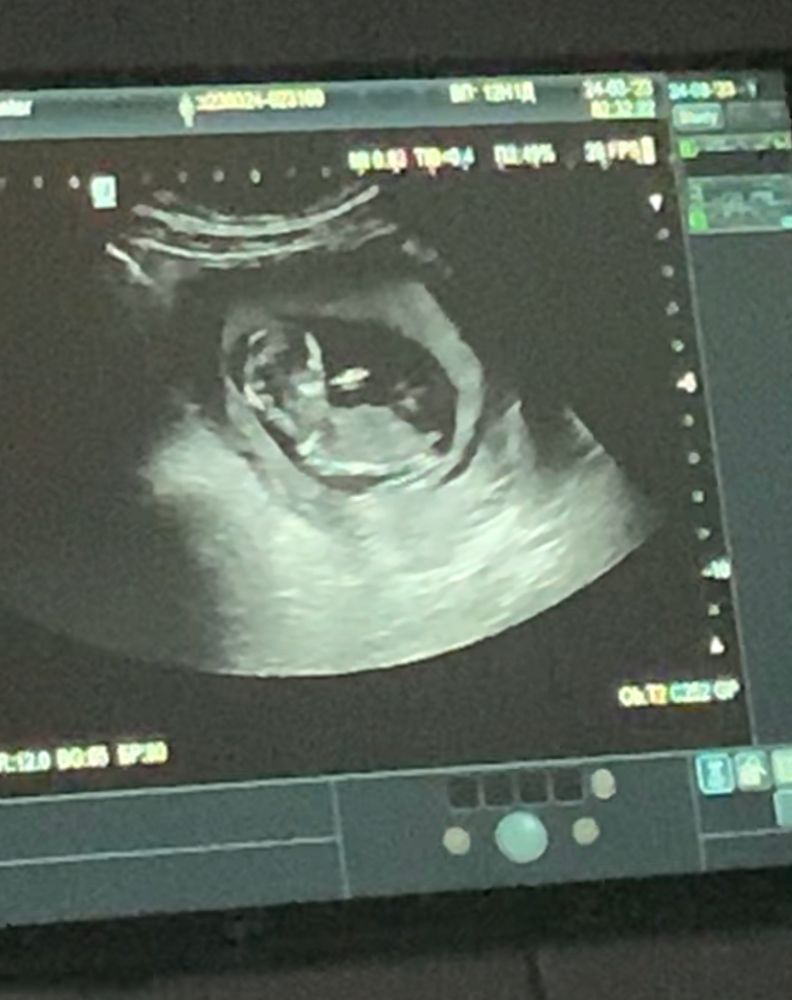

На узи сказали, что девочка. Очень хотела мальчика. Посмотрите, может что перепутали?

В 12 недель точность невелика, тем более угол наклона полового бугорка у вас неоднозначный. На первом фото ближе к парню мне кажется.

Наталья, мне тоже кажется, что мальчик. Видимо это самовнушение уже. Была у двух узистов, оба в один голос говорят что девочка. Я прекрасно понимаю, что это замечательно и надо радоваться, но не лежит у меня душа. Корю себя за это